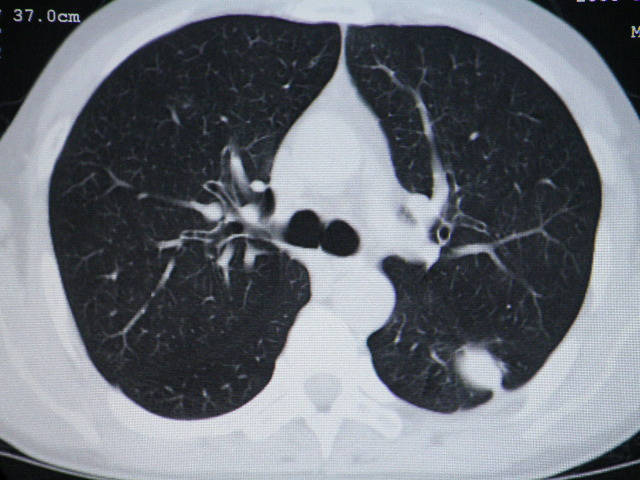

左肺下叶背段软组织结节,偏心空洞,周围见长纤维所条及卫星灶,首先考虑结核球,周围型肺癌待排。

左肺下叶偏心软组织肿块,边缘毛刺征,胸膜凹陷征

左肺下叶偏心软组织肿块,边缘毛刺征,胸膜凹陷征,血管集束症

肺内结节在纵隔窗内测ct值为43hu